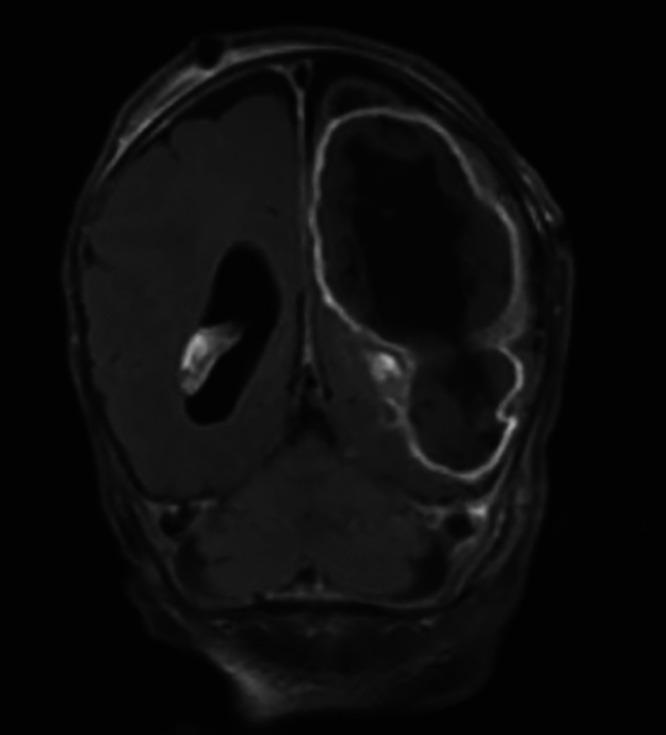

Cronobacter brain abscess and refractory epilepsy in a newborn: role of epilepsy surgery. Illustrative case.

The authors report a unique case of neonatal Cronobacter meningoencephalitis complicated by brain abscess and status epilepticus, requiring surgical intervention in a preterm 4-week-old male and related to contaminated powdered infant formula. They discuss the medical and surgical management in this patient, as well as the role of epilepsy surgery in acute drug-resistant epilepsy. This is paired with a literature review examining Cronobacter infections in infants to provide a summative review of the existing literature.

Cronobacter contamination in powdered infant formula and breast pumps is rare but can cause life-threatening infections. When evaluating patients with Cronobacter central nervous system infections, serial neuroimaging, infection control, and prompt surgical management are essential. Future studies are needed regarding the role of epilepsy surgery in the acute infectious period.